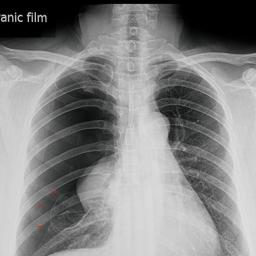

Een long kan soms inklappen. Spontaan, of na een ongeluk, door ziekte of bijvoorbeeld blowen.